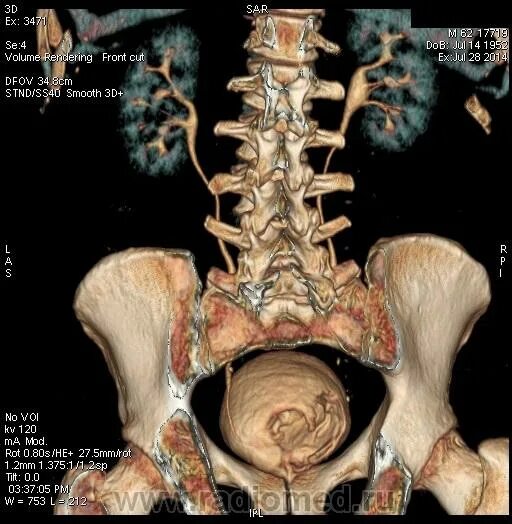

Где можно сделать кт малого таза